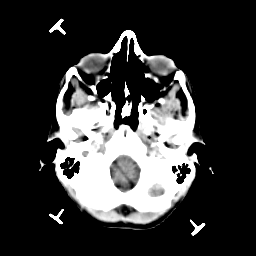

Metastatic bronchogenic carcinoma: Roentgen-ray CT -- Slice #2

[Home][Help][Clinical] Slice 2